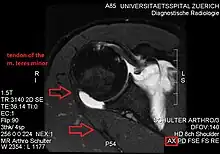

Imaging

Conjoint and intact tendon disc of teres minor and infraspinatus muscle.

Intact teres minor tendon with physiologically hypointense signal.

Hyperintense, fatty degenerated teres minor muscle.

Ultrasonography is a tool to detect a fatty degenerative atrophy of the teres minor and shows in affected muscles increased echogenicity and betimes a slight reduction in muscle bulk. MR imaging helps to consolidate the diagnosis of neurogenic muscle atrophy. Extracellular edema after traumatic events causing neural damage show an increased signal intensity on T2-weighted MRI sequences and normal intensity on T1-weighted sequences. Posterior humeral circumflex artery compression and reduced blood flow in stressful arm positions and or maneuvers can be diagnosed by a Doppler ultrasonography. The nerve should be detected adjacent to the vessel. In an elevated arm position the axillary neurovascular bundle can be seen at the posterior axillary fold just before it perforates the deltoideus, while the posterior course is well visible in the neutral position. For a detailed assessment of the artery, a MR angiography is required. The major task of an ultrasonographic examination is to rule out any space occupying mass. Additional electromyography is helpful to reveal any decelerated nerve conduction velocity, and thus denervation of the concerned muscle.[6]